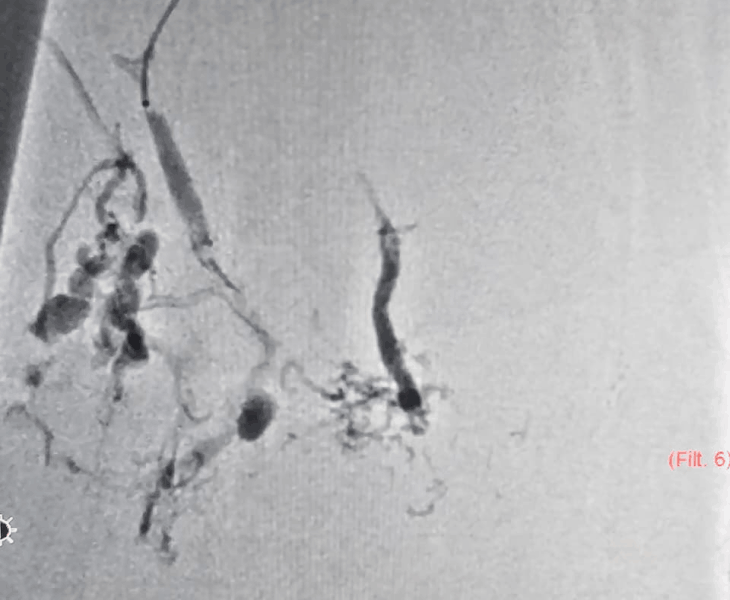

Large vascular malformation in leg

2. Image‑Guided Treatment

Depending on the lesion, we perform embolization and/or sclerotherapy to reduce abnormal flow and shrink the malformation in a controlled manner.